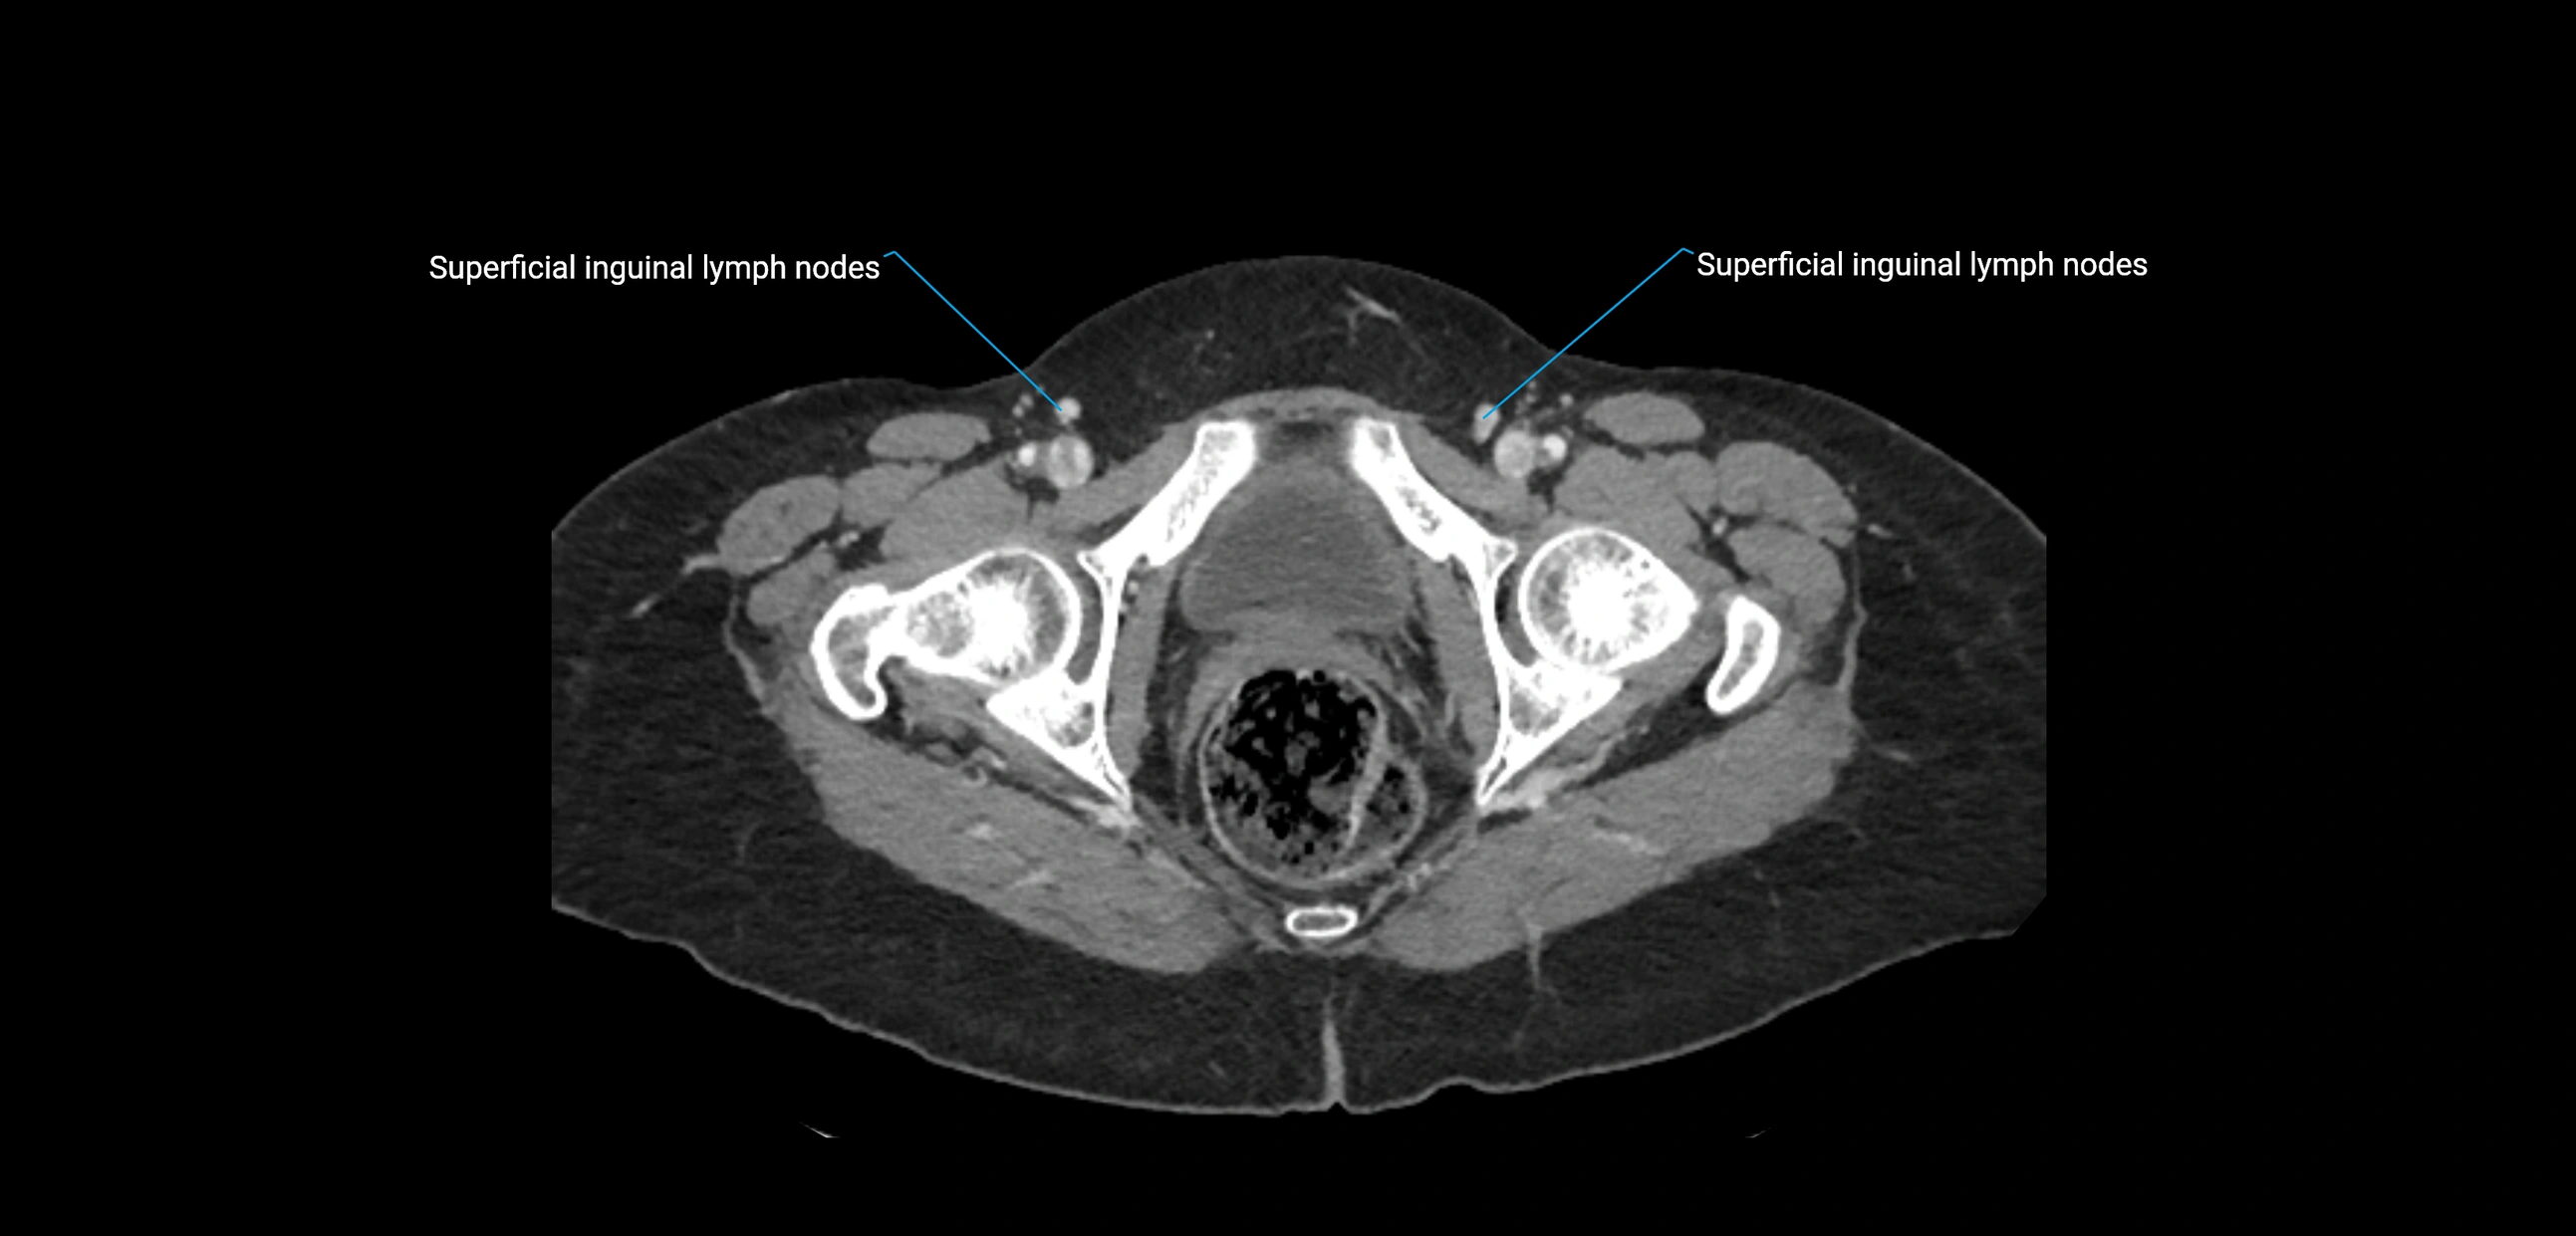

CT Appearance

CT Post-Contrast:

• Normal nodes enhance homogeneously

• Malignant nodes may show heterogeneous enhancement, central necrosis, or conglomerate formation

• Size >1 cm short axis is suspicious, though morphology and distribution are equally important